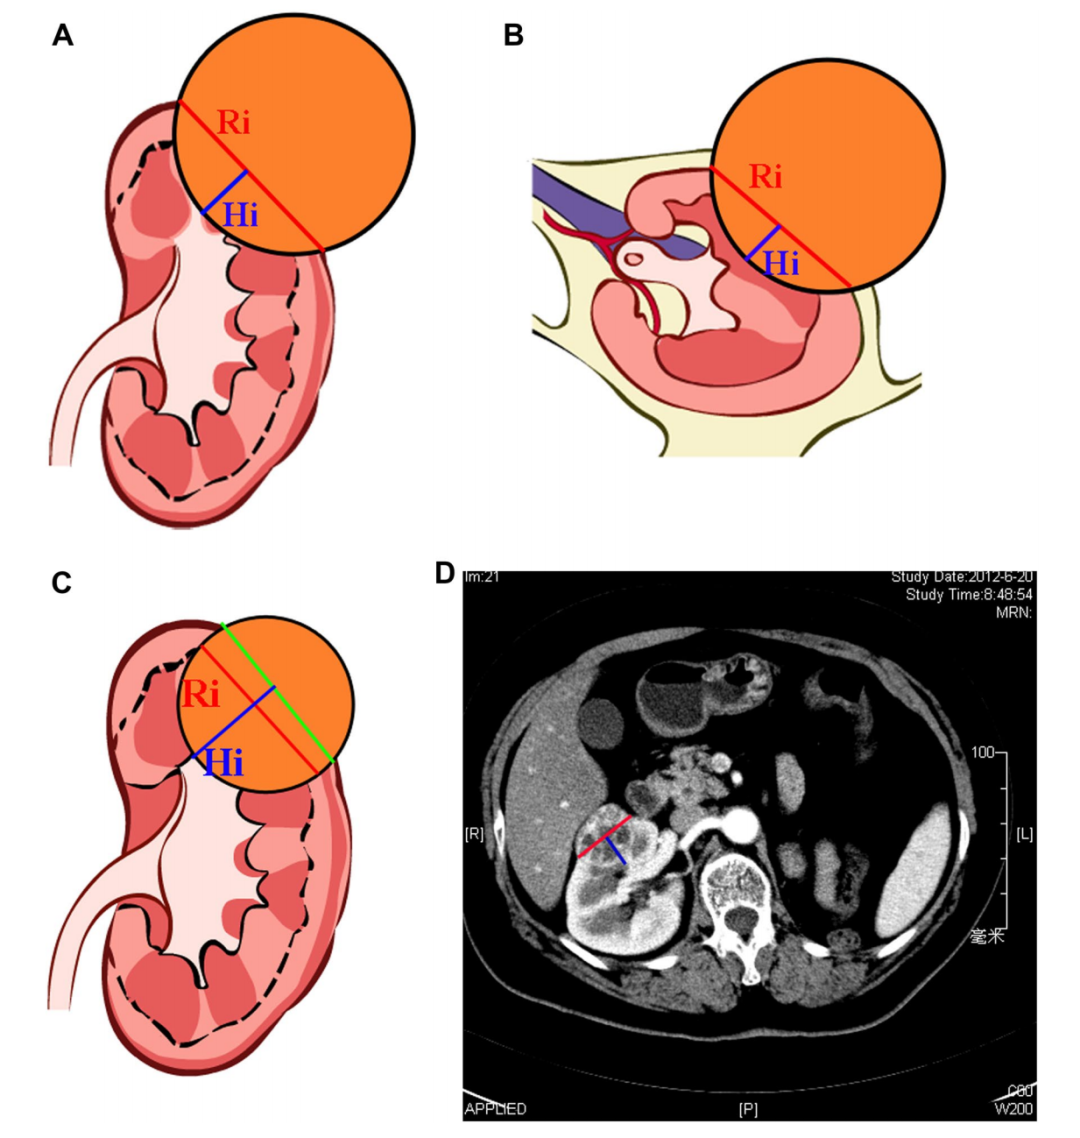

郭剑明教授:在手术评分系统领域方面,国外的RENAL、PAUDA评分系统根据肿瘤的最大半径分为X≤4cm、4cm<X<7cm、X≥7cm,但单凭肿瘤的大小不能决定手术难度,例如最大半径为4cm的肿瘤,其中有3.5cm都长在肾脏外面,只有0.5cm在肾内,这种外凸形的肿瘤切除手术往往比较容易;相反有3.5cm都长在肾脏里面,外面只有0.5cm,这种内生型的肿瘤手术难度和风险就大得多。而这两种情况在RENAL、PAUDA评分系统中难以区分,这也是RENAL、PAUDA评分系统最大的缺陷。

鉴于此,我们团队通过学习相关经验,基于庞大的肾癌数据库以及多年的手术经验,提出了中山评分系统的方案。该评分系统以肾内最大肿瘤直径(Ri)为评价核心,并评估肿瘤位置(Loation)和肿瘤深度(Depth)等指标。评分越低代表手术时间短,出血量少,并发症少,复发率低,避免了国外比较粗浅的分类方式,证明了我们的评分系统的科学性,得到了国际上的广泛认可。

肾癌手术的中山评分系统ZS Score(Medicine. 2015)

中山评分系统是我国自主研发的评分系统,还是比较引人注目的;但外国人习惯使用以往的评分标准,所以在国际上推广起来比较困难。然而,我们的评分系统非常科学,是以肾脏内最大肿瘤直径为主要依据,肿瘤直径用CT测量即可,美国的研究人员也进行了类似的评分系统研究,但其研究是以肿瘤覆盖肾内的面积为依据,需要经过复杂的计算,因此实用性较差。